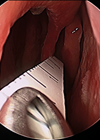

Endoscopic arytenoid abduction lateropexy for bilateral vocal cord paralysis in neonates

We are delighted to publish a further update on the use of the technique for vocal fold lateralisation in neonates from Laszlo Rovo and Shahram Madani, who have previously informed us of this new technique [1]. These cases are rare...